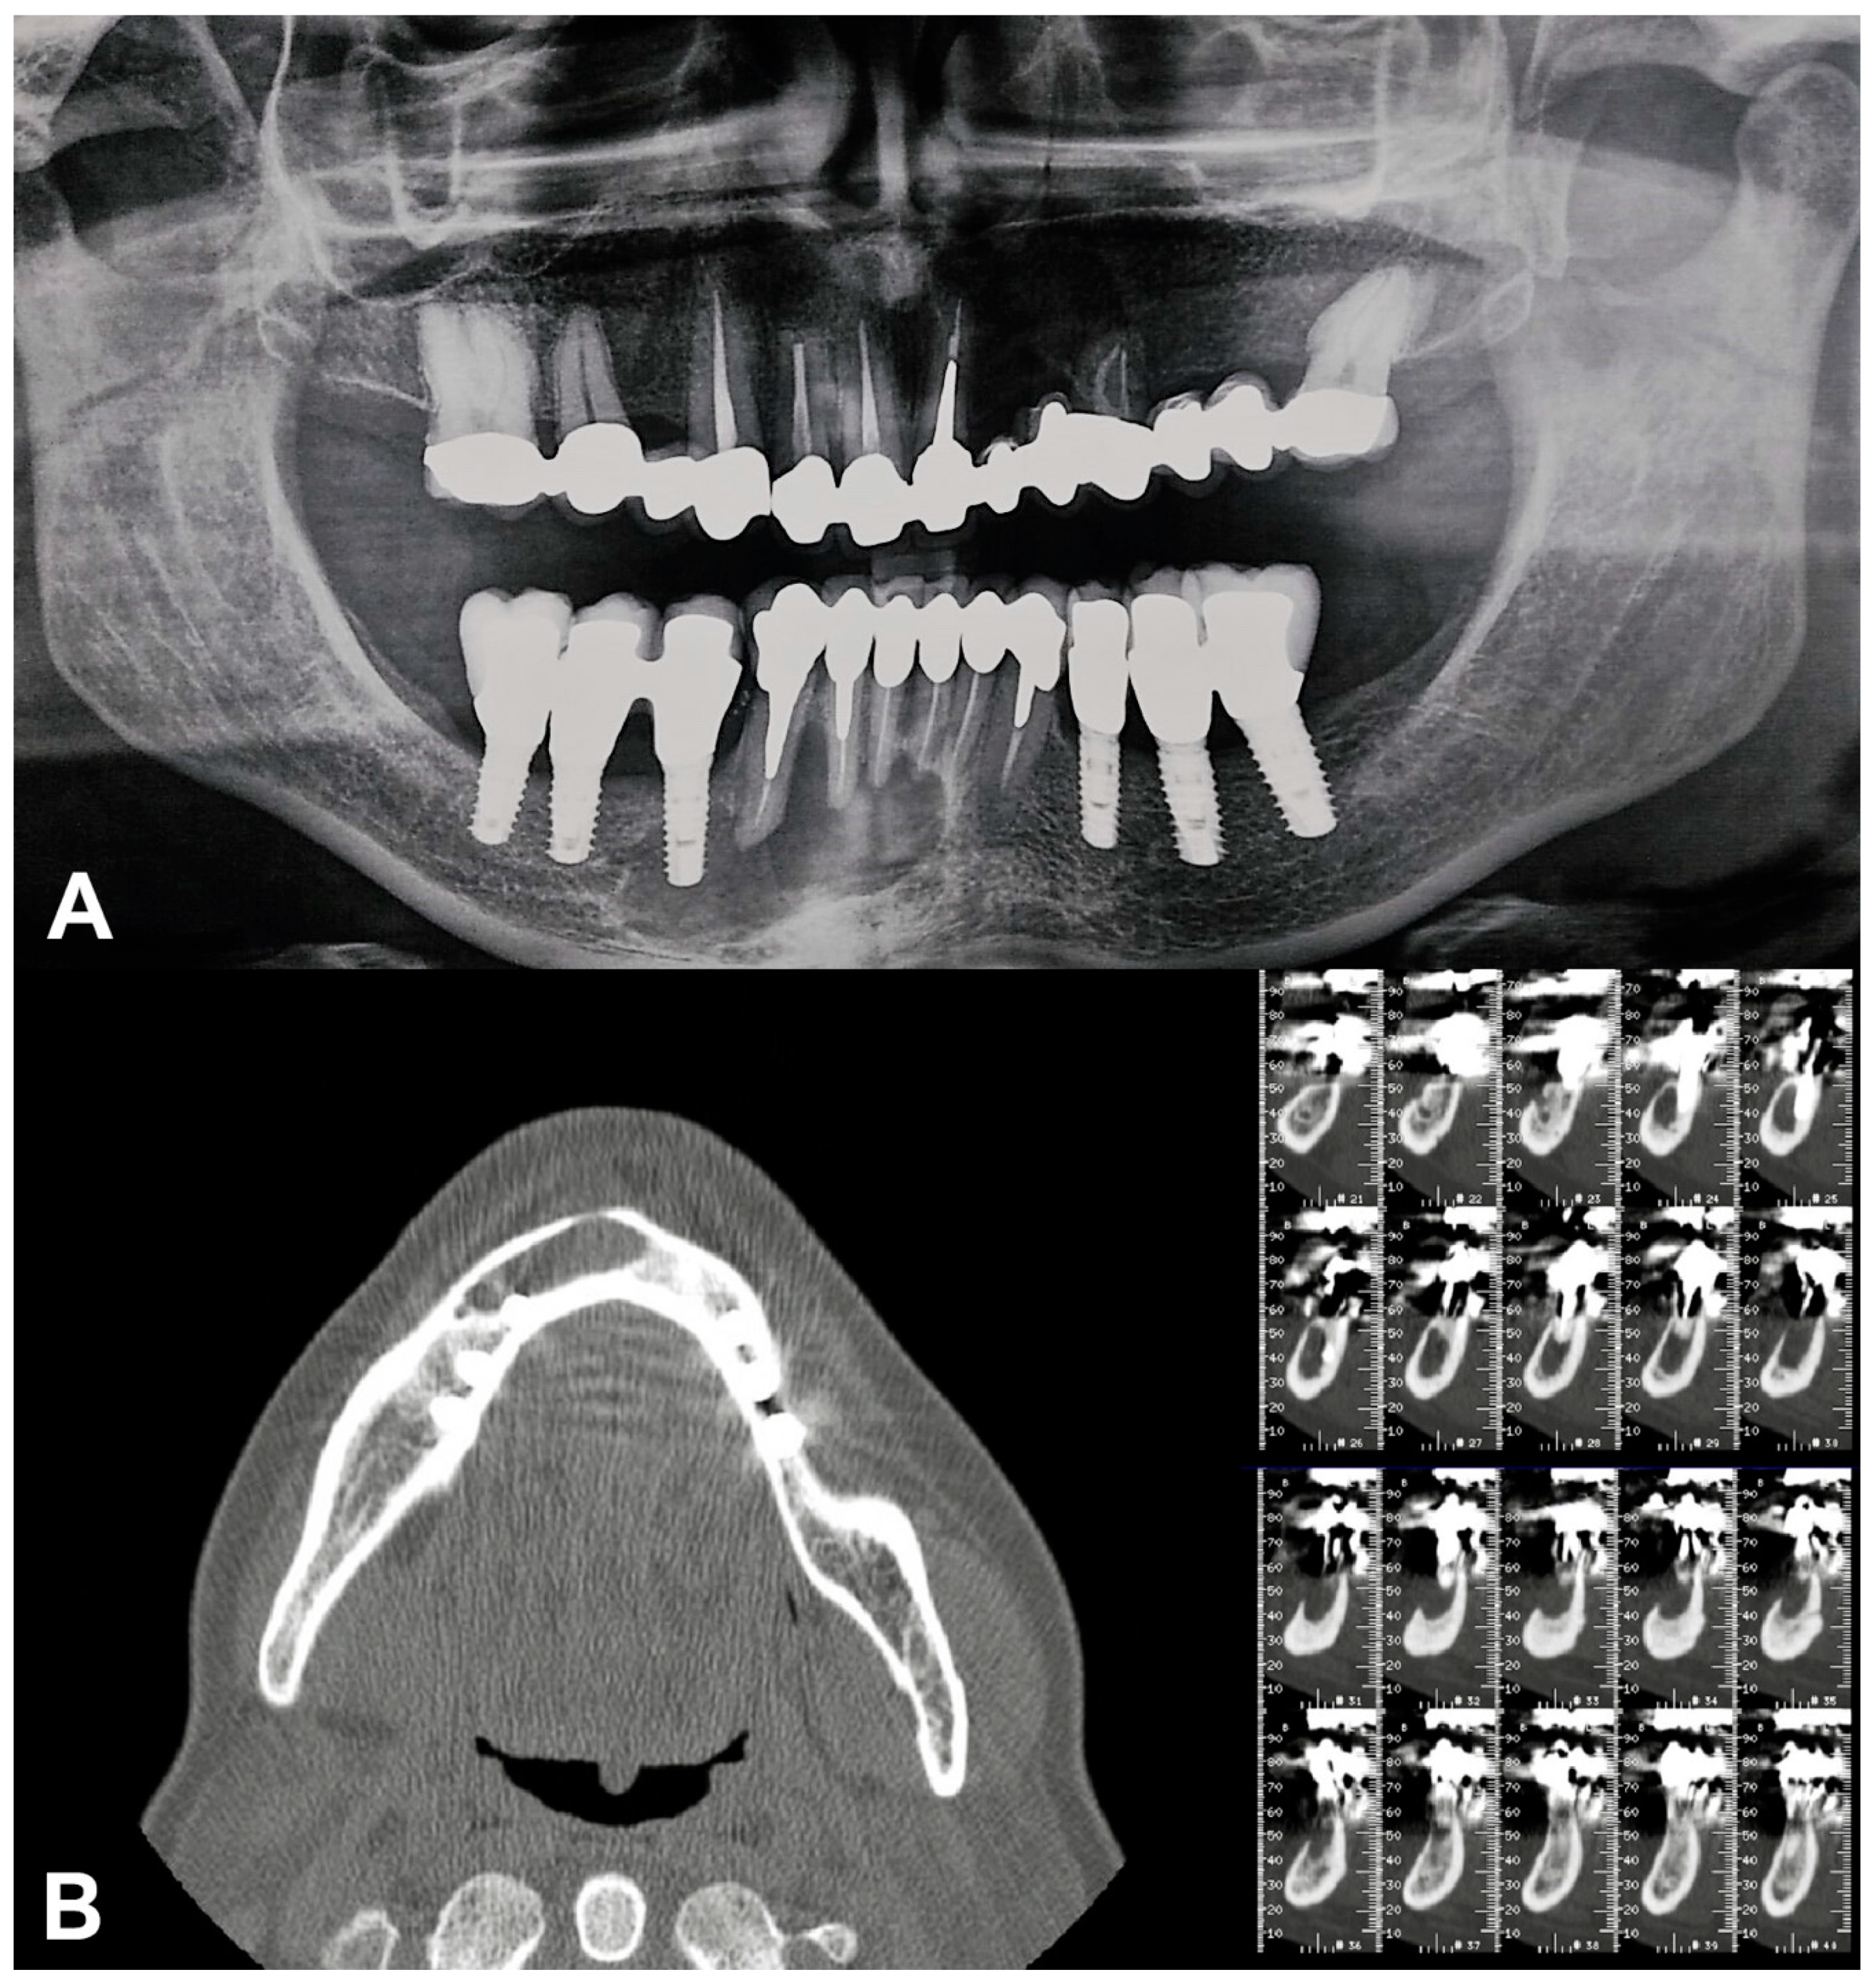

2. Case Report

- Implant-supported prostheses from 3.4 to 3.6 and from 4.4 to 4.6.

- Prosthetic rehabilitation on dental support from 3.3 to 4.3. Metallic endocanalar posts in 3.3, 4.2, and 4.3.

- Endodontic treatment on 3.1, 3.2, 3.3, 4.1, 4.2, and 4.3.